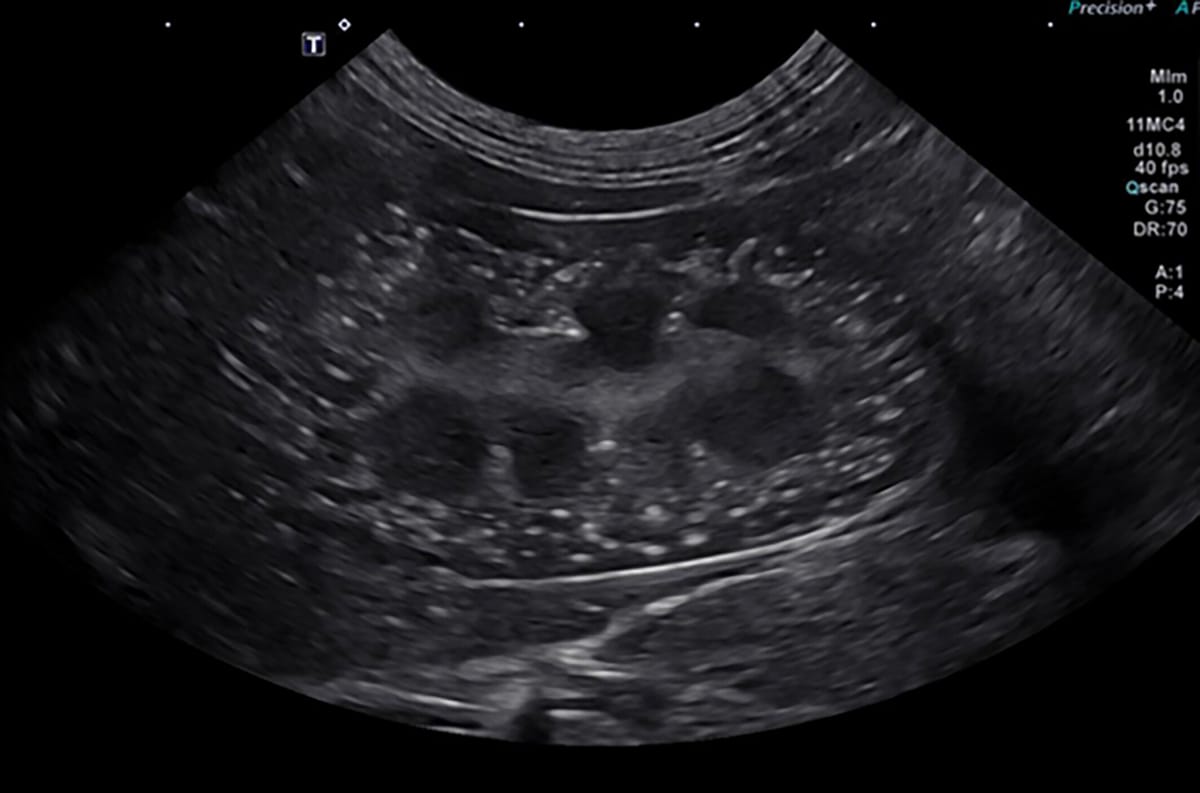

In dog 1, thoracic radiographs indicated moderate to severe interstitial to broncho-interstitial infiltrates in both dogs. Abdominal ultrasound examination identified a mildly enlarged, hyperechoic liver, mild hepatic lymphadenopathy, bilateral nephrocalcinosis, and mild splenic microlithiasis.

Ultrasound imaging on dog 1 on the day of admission demonstrating severe nephrocalcinosis.